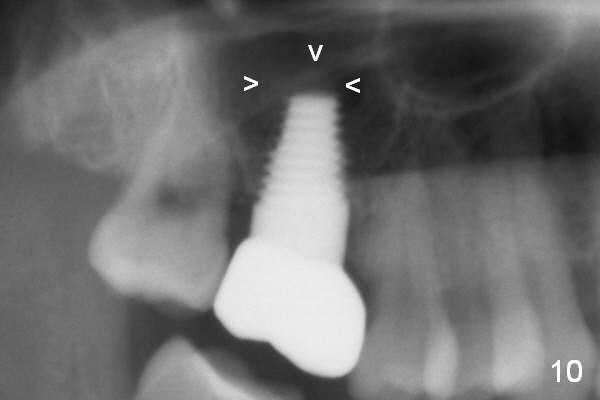

Our experience demonstrates higher failure rate associated with shorter implant in this situation. The depth of the osteotomy is then increased to 14 mm using the same series of osteotomes and taps. The bone at the top of the osteotomy finally wears off when the last tap is applied (7x17 mm). But the sinus membrane is intact. Osteogen is pushed into the osteotomy before placing a 7x14 mm implant with insertion torque > 60 Ncm (Fig.5). The implant contacts the gingiva tightly; no suture is necessary. There is no intra- or postop nasal hemorrhage. The wound heals 8 days postop (Fig.6). There is bone surrounding the apical portion of the implant in the sinus (Fig.7,8 *) 3.5 months postop. The implant is stable. There appears no crestal bone resorption 7.5 months post cementation (Fig.9 ^). Sinus lift is visible 16 months post cementation (Fig.10 (trimmed panoramic X-ray) arrowheads). There is discomfort between #2 and 3, probably due to poor oral hygiene. There is no deep pocket or bone loss (Fig.11, 26 months post cementation).